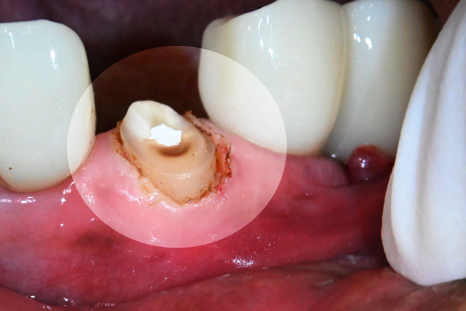

사진을 보시면 우측 윗쪽 앞니의

머리 부분이 온전히 부러졌습니다.

단순히 눈으로 보거나 기구로 만져 반응을 평가하는 것만으로

어떤 상태인지 평가하긴 어렵습니다.

그래서 Panorama나 CBCT 같은 자료를 통해

내부 상태를 확인하게 됩니다.

당산동 치과 에서 준비한 사진을 보시면

안쪽 신경이 외부로 드러난 것을 확인할 수 있습니다.

파절 범위가 넓어 치수까지 침범했는데,

아직까지 염증 반응은 없었습니다.

만약 신경 손상이 심하거나 광범위한 영역에

염증이 만들어졌더라면 발치까지 고려되었을 텐데

아직 자연치 보존이 가능하다 판단되어

신경치료를 통해 개선 가능하다 판단됩니다.